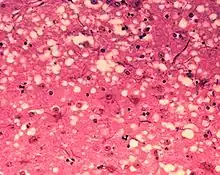

D'un point de vue anatomopathologique, on observe ainsi au niveau de l'encéphale la formation de vacuoles (donnant un aspect spongieux au cerveau, d'où le nom de spongiforme dans ESST), une mort des neurones, une gliose (multiplication des astrocytes et de la microglie) et l'accumulation d'une protéine de l'hôte, la PrPC (abréviation de protéine prion cellulaire, l'isoforme normale), sous une conformation anormale (ou mal repliée) alors dénommée PrPSc (abréviation de protéine prion de la scrapie)[6].

Les « trous » microscopiques sont caractéristiques des tissus infectés de prions, leur donnant une consistance spongieuse.

1. La mise en évidence d'une triade de signes neuropathologiques (perte neuronale, astrogliose, vacuoles spongiformes) ;